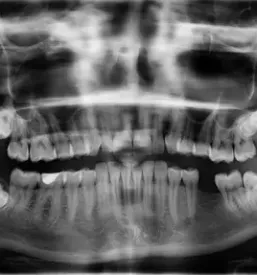

Vas vedno očara lep in zdrav nasmeh? Bi ga želeli imeti tudi sami?

Naše delo je naše poslanstvo. Zavedamo se, kako pomembni so zdravi zobje za zdravje in samozavest posameznika, zato uporabljamo le najboljše materiale, aparate in pripomočke, kar lahko potrdi že veliko naših zadovoljnih strank in odličnih referenc. Dober privat zobozdravnik v Mariboru je sedaj na voljo tudi vam! Zavedamo se, da je strah pred obiskom zobozdravnika zelo pogost pojav, zato smo pri delu vedno nežni, razumevajoči in pristopamo brez kakršnegakoli obsojanja. Težave z zobmi se lahko pojavijo pri komurkoli - mi smo tukaj, da naredimo vse, kar lahko, da jih odpravimo.

Ker smo dober privat zobozdravnik, Maribor že zelo dobro pozna naš pristop k delu in storitve, ki med drugim obsegajo: